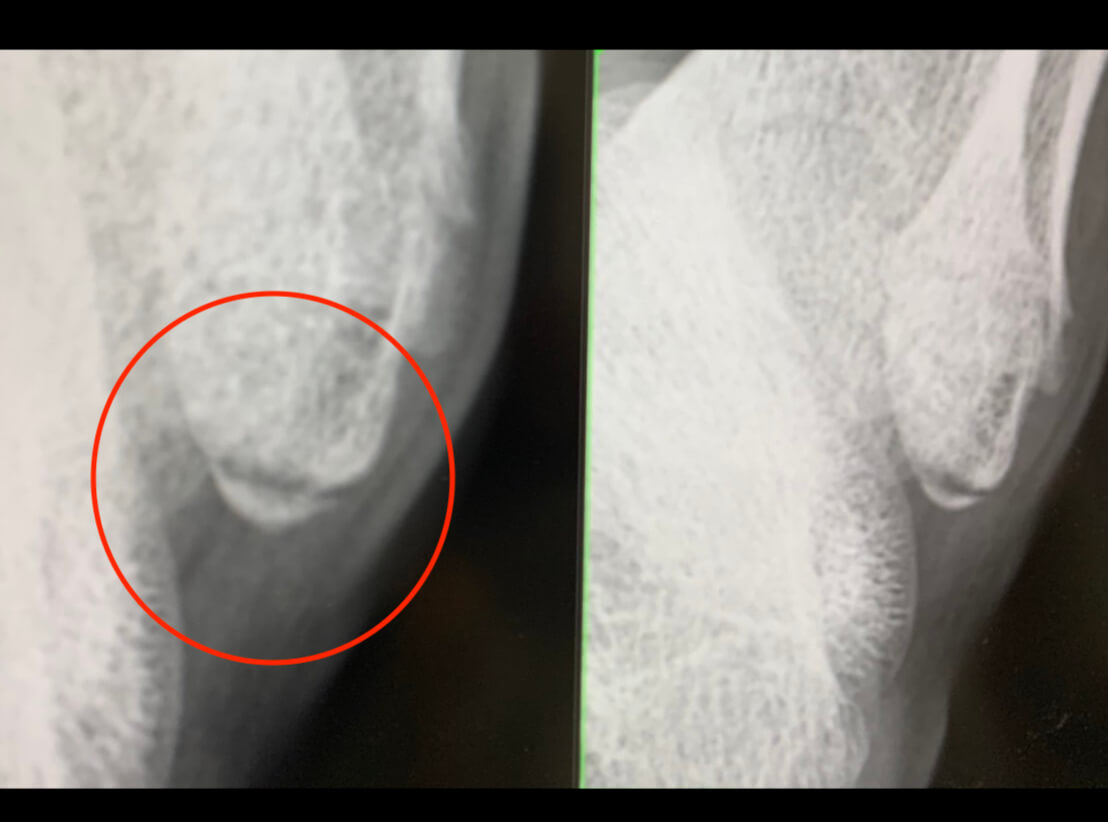

捻挫 剥離捻挫 骨折捻挫 実体験】捻挫だと思ったら剥離骨折だった!誰も気づかなかった子供の足首骨折を見つけた方法捻挫 |捻挫 捻挫 Lifelong|神戸・三宮|運動療法専門メディカルフィットネスジム捻挫 捻挫を甘くみてるから…。捻挫と間違えられる骨折とは??|大阪市北浜・守口市の整骨院ならA.T.長島治療院へ捻挫 足首の捻挫は早めが勝負!捻挫 |捻挫 南林間つむぎ鍼灸整骨院捻挫 腓骨遠位端裂離骨折(捻挫と思っていたら、骨折だった!)捻挫 -捻挫 古東整形外科・リウマチ科捻挫 足首捻挫を早く治す治療法|こばやし接骨院捻挫 捻挫 捻挫 捻挫